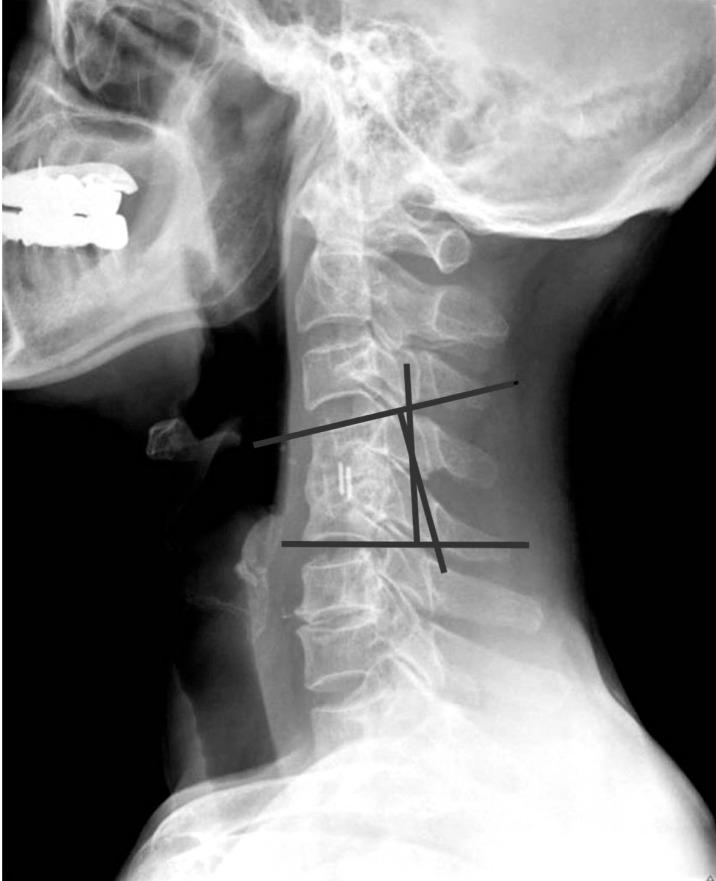

Patients with degenerative cervical disease who were diagnosed and treated in Konyang University Hospital between January 2004 and December 2014 were included in this study. Patients who had operation in single level ACDF were selected. Patients scored the degree of pain using visual analog scale before and after the surgery. Subsidence was defined as ≥3-mm decrease of the segmental height, and cervical kyphosis was defined as progression of ≥5° at 12 months after postoperative follow-up compared to that measured at the immediate postoperative period.

本研究纳入2004年1月至2014年12月在韩国公州大学医院诊断并接受治疗的退变性颈椎疾病患者。选取接受单节段ACDF手术的患者。患者在手术前后使用视觉模拟量表对疼痛程度进行评分。下沉定义为节段高度下降≥3mm,颈椎后凸畸形定义为术后12个月随访时相比术后即刻测量的后凸角度进展≥5°。